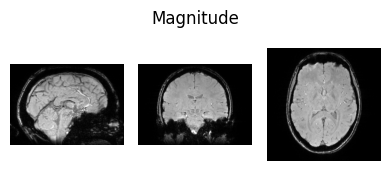

Inspect input data#

Here we define a function we will use to visualise NIfTI images so we can view some of the input data:

show_nii(glob("bids/sub-*/ses-*/anat/*mag*T2starw*nii*")[0], title="Magnitude", vmax=500)